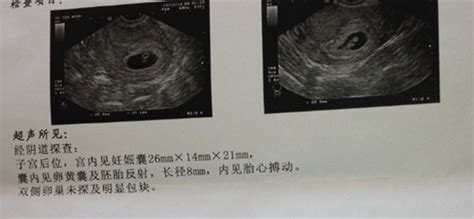

怀孕8个月的B超数据

根据孕周表,您的宝宝双顶径和骨长,也就是头部横径和大腿骨长都发育正常,胎心和羊水深度也在范围值内,脐带血阻比也正常。

怀孕八个月B超结果如下:双顶径80mm.胎心率132次/分,股骨长59mm,羊水深约61mm,内透声好。胎盘附于子宫前壁,厚约28mm,绒毛板轻度起伏。这样正常吗,知不知道有几斤?谢谢

2000克左右!

31周左右,一切正常!